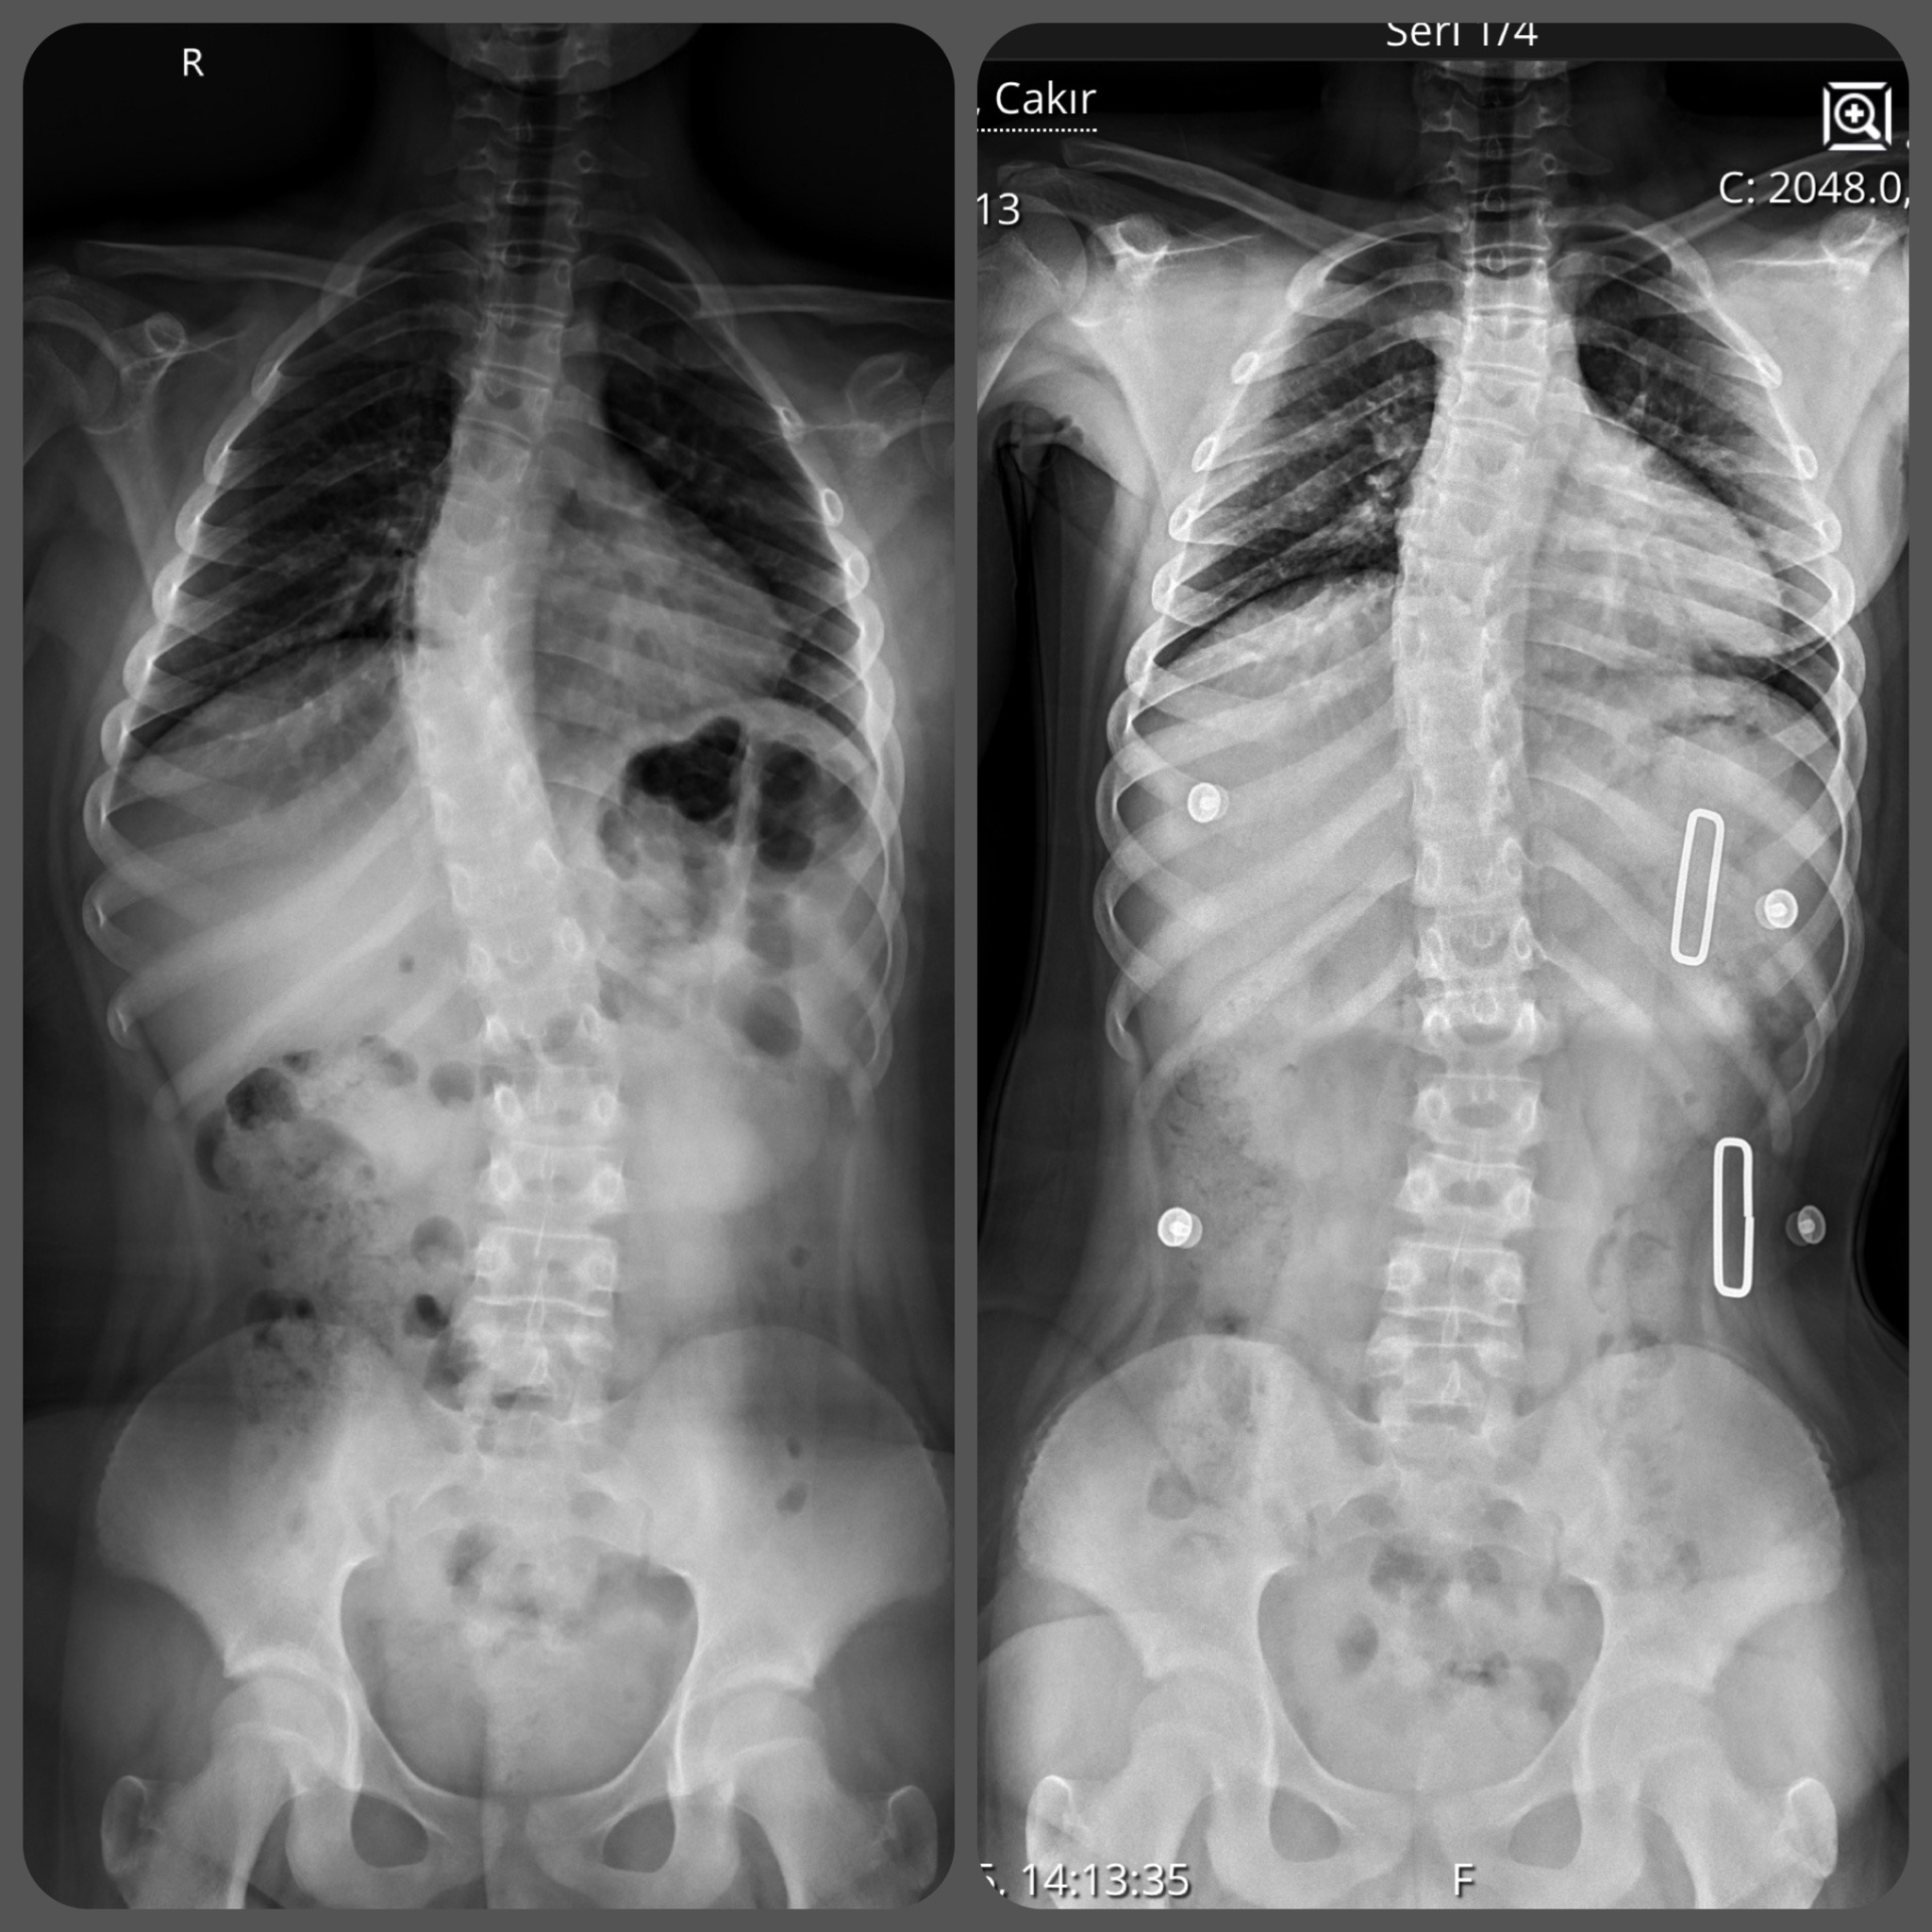

CAD/CAM (Bilgisayar Destekli Tasarım) sistemlerimizle, röntgen üzerindeki eğrilik derecesine (Cobb açısı) tam zıt kuvvet uygulayan, asimetrik Gensingen/Cheneau tipi korseler tasarlıyoruz.

Uyguladığımız 3D korseler ile elde ettiğimiz düzeltme sonuçlarından bazı örnekler.